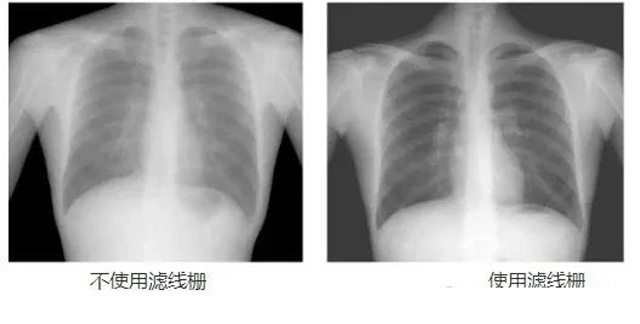

DR影像X射線在醫學檢查成像有著廣泛的使用。但是它的散射線影響成像質量問題。濾線柵的發明使用很好的解決了這個問題,構造簡單鉛條粗,密度和柵比規格單一,能減散射線但吸收較多原發射線。伴隨這醫療影像設備技術的發展,這個濾線柵的工藝制造技術有改進,鉛條變薄,柵密度和柵比有更多的選擇。特別是材料方面有新組合,填充物也依不同成像要求優化。特別是移動DR這類型的DR設備的出現,濾線柵也設計成立方便拆卸形的,方便使用。被照體情況決定是否使用,更好平衡成像質量與射線劑量。

放置方面:置于人體與片盒間,聚焦面朝向X線入射方向,X線焦點放鉛條會聚線上,不能反置,X線中心對準濾線柵中心,左右偏移不超3cm,傾斜X線管要與鉛條排列方向平行。攝影時焦距改變不超焦距的25%;活動式濾線器運動時間至少長于曝光時間的1/5;因吸收原發射線要適當增加曝光條件;四肢薄位置一般不用濾線柵;不同千伏對應不同柵比;立位胸片架、乳腺DR攝影等有各自特定濾線柵要求。